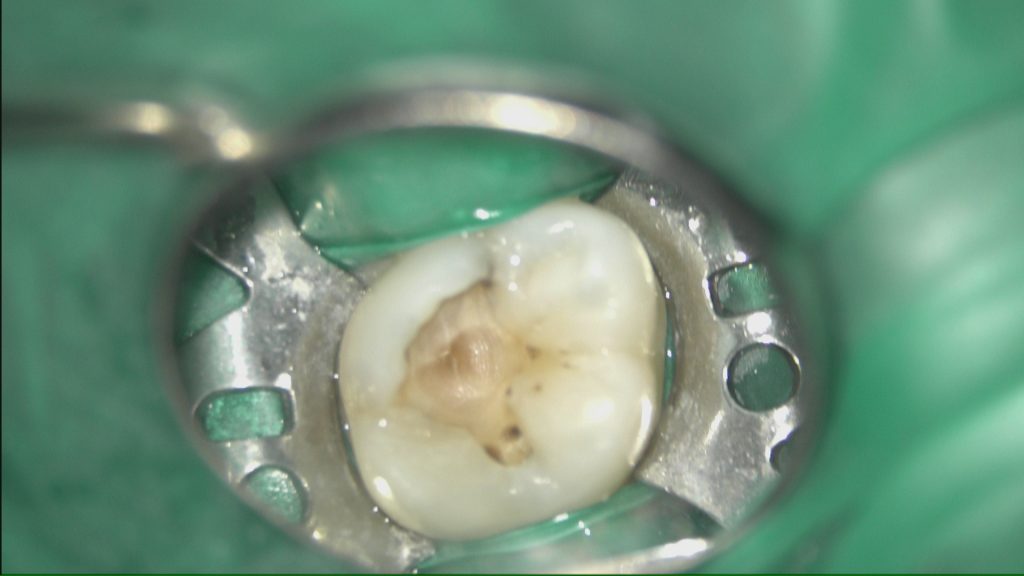

初診時です。

カリエス(虫歯)が大きく神経まで到達しております…